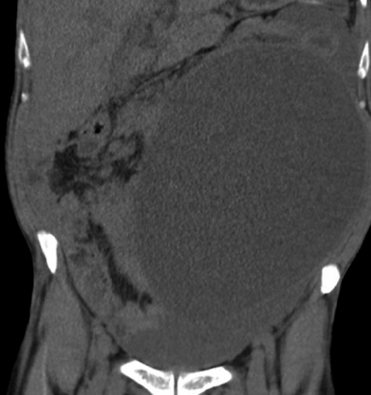

Imágenes y Cirugía

![]() |

Camila Valenzuela Labra, Raúl Valenzuela Labra, Jaime Cruz Fuentes, Matías Orellana Pérez, Marcelo Villarroel Soto, Hernán Valenzuela Valenzuela